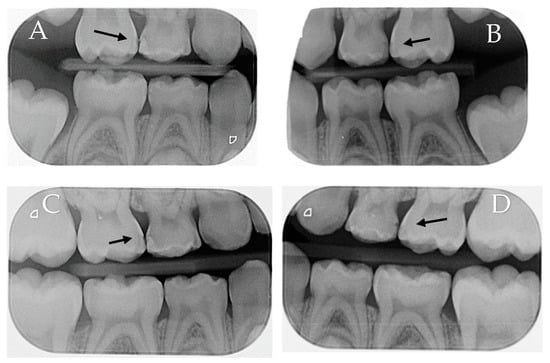

The third screening phase was comprised of a direct visual clinical examination to assess the cavitation status of the proximal carious lesions that were deemed qualified in the second phase. To enable direct visual clinical examination of the proximal surfaces, orthodontic elastic separators were placed in the eligible interproximal areas. The children returned after two days, and the temporary separators were removed. The selected proximal surfaces were cleaned using a prophy cup (Prophy Cup, Snap-on, Guangzhou Jaan Medical CO., Guangzhou, Baiyun, China) and dental floss (Dental Floss, non-waxed, Oral-B Laboratories, Iowa City, IA, USA). The surfaces were examined by the gentle running of a community periodontal index (CPI) probe across the lesion to assess cavitation. Figure 1 shows an illustration of the clinical examination steps. Then, carious lesions were clinically scored, from the lingual, buccal, and occlusal sides, with the International Caries Detection and Assessment System II (ICDAS II) [16], with a score of (0) indicating clinically sound surfaces; (1 and 2) were non-cavitated lesions with score 1 lesions requiring air-drying to see the lesion, while the lesion could be seen without air-drying in score 2; (3) there was a localized breakdown in the enamel because of caries, but the dentin was not visible; (4) had a dark underlying dentin shadow with or without a localized enamel breakdown; (5 and 6) had dentine cavitation with increasing stages. The surfaces were scored by the two trained and calibrated examiners independently (.JK. and O.F.). If there was disagreement in the scores between the first two examiners, a third (S.B.) calibrated and trained examiner was asked to assess the lesion. The Kappa’s values for the inter-examiner (0.869) and intra-examiner reliability (0.867–0.870) for the direct visual clinical examination indicated very good agreement between the examiners. During the clinical examination, all examiners were blinded to the radiographic score of the lesions. Any child diagnosed with a cavitated proximal carious lesion (ICDAS II score of 3 or more) by at least two of the examiners was excluded and referred for restorative treatment. Children with at least one pair of primary molars in contralateral quadrants with matching non-cavitated proximal carious lesions diagnosed radiographically as E1, E2, and D1 and clinically as an ICDAS II score of 1 or 2 were considered eligible for the study.

In terms of lesion cavitation, ten lesions (13.4%) (eight scored 3 (10.7%), two lesions scored 4 (2.7%)) in the experimental group, and nine lesions (12.0%) in the control group exhibited clinical cavitation and required restorations at the six-month follow-up visit. However, at the 12-month follow-up visit, twelve lesions (17.2%) in the control group were clinically cavitated (nine (12.9%) scored 3, two (2.9%) scored 4, and one (1.4%) scored 5 and 6), compared to just three lesions (4.3%) that scored 3 in the experimental group. A clinical examination example of assessing the lesions is shown in Figure 3.

Figure 1. Clinical examination steps. (A) Separators in place for two days.; (B) separators removed after two days, and space created; and (C) CPI probe was used to verify cavitation.